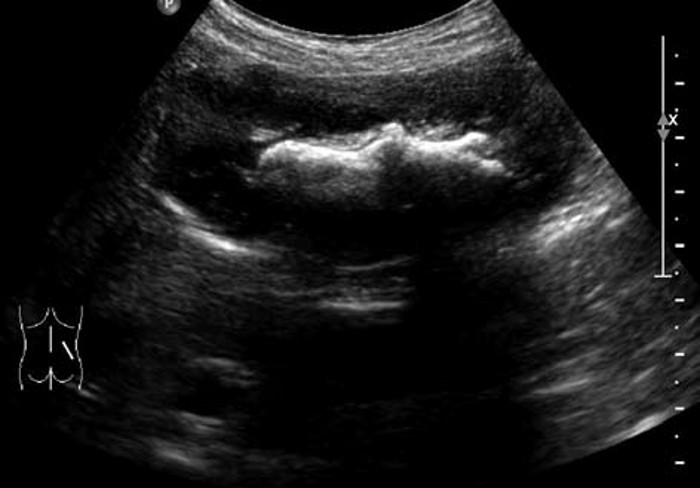

肾结石的超声图像,肾结石超声诊断及鉴别 2. 中等结石:高强团状回声一般呈新月状,后方声影明显。尿酸、胱氨酸、黄嘌呤结石较疏松,隐约可见光团全貌,后方声影浅淡。

3. 鹿角状结石:大而分叉,形态不规则,超声往往仅显示局部突起的表面,呈几个孤立的强光团或弧形强回声带,像多个结石,但连续扫查可出现互相连续的一体。

肾结石的超声图像,肾结石超声诊断及鉴别 4. 肾结石合并积水:近端扩张积水,如肾盏颈部梗阻引起肾盏扩张,肾盂输尿管连接部梗阻则表现肾盂,甚至肾盏扩张积水。如发现有随体位改变移动的小结石,提示下方多有结石嵌顿,应追踪扫查,明确引起梗阻的原因。